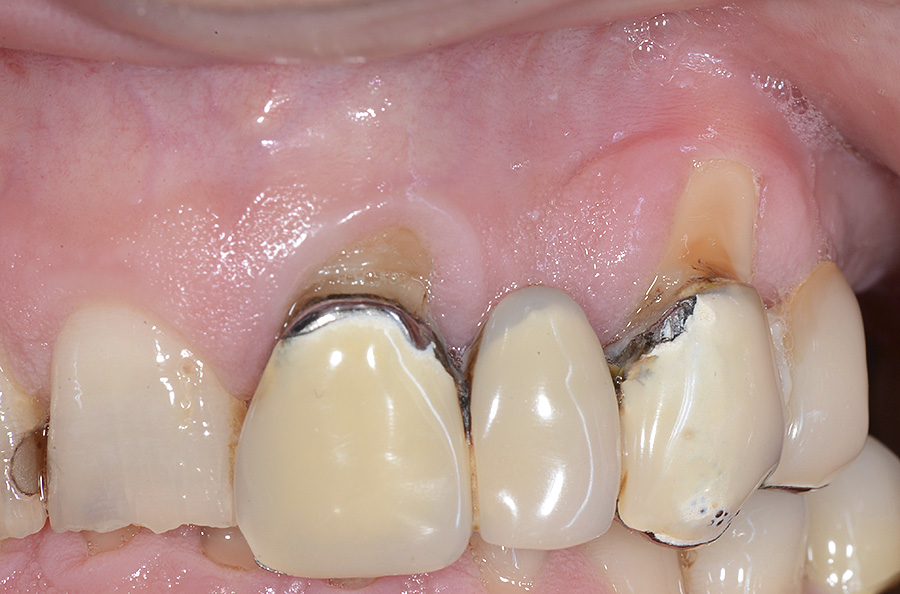

PREMESSA: in seguito all’estrazione dell’incisivo laterale superiore di destra, resasi necessaria per cause batteriche, si decide di affrontare il caso con il posizionamento di un impianto in sostituzione dell’elemento mancante dopo guarigione del sito infetto. Con tecniche rigenerative sia dei tessuti ossei mancanti a causa dell’infezione pregressa, sia dei tessuti gengivali che appaiono inizialmente troppo spostati in alto, si ripristina una corretta morfologia delle parabole (contorni) gengivali e delle papille interdentali (triangoli di gengiva tra due denti vicini).

Vengono utilizzati 2 tipi di provvisori: il primo, cementato ai denti vicini, viene utilizzato dal momento dell’estrazione del dente fino ad impianto osteointegrato (circa 6 mesi); il secondo, avvitato direttamente all’impianto, ha una funzione di prova estetica ma soprattutto di guida per la maturazione dei tessuti gengivali peri-implantari portandoli verso la maturazione completa prima di posizionare la corona finale in disilicato di litio.